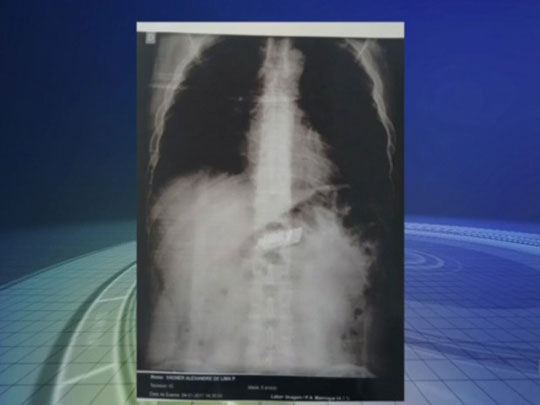

Preso passa por cirurgia para retirada de celular do estômago Foto: Reprodução/TV TEM

Um preso da penitenciária de Mairinque (SP) passou por uma cirurgia no Hospital Regional, em Sorocaba (SP), neste sábado (7), para a retirada de um celular no estômago. Segundo a Secretaria de Administração Penitenciária, um exame de raio X comprovou o aparelho. A descoberta foi durante uma revista nas celas esta semana. Ele passou pelo procedimento e está hospitalizado. De acordo com o G1, a secretaria informou que tinha uma denúncia de celulares na cela mas não encontrou nada. Só que o comportamento estranho dos presos chamou a atenção e alguns foram levados para o hospital para exames de radiografia.